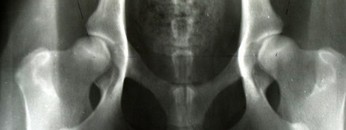

C - dysplazja nieznaczna i niebudzące wątpliwości, wyraźne odchylenie od normy

C - dysplazja nieznaczna i niebudzące wątpliwości, wyraźne odchylenie od normy.